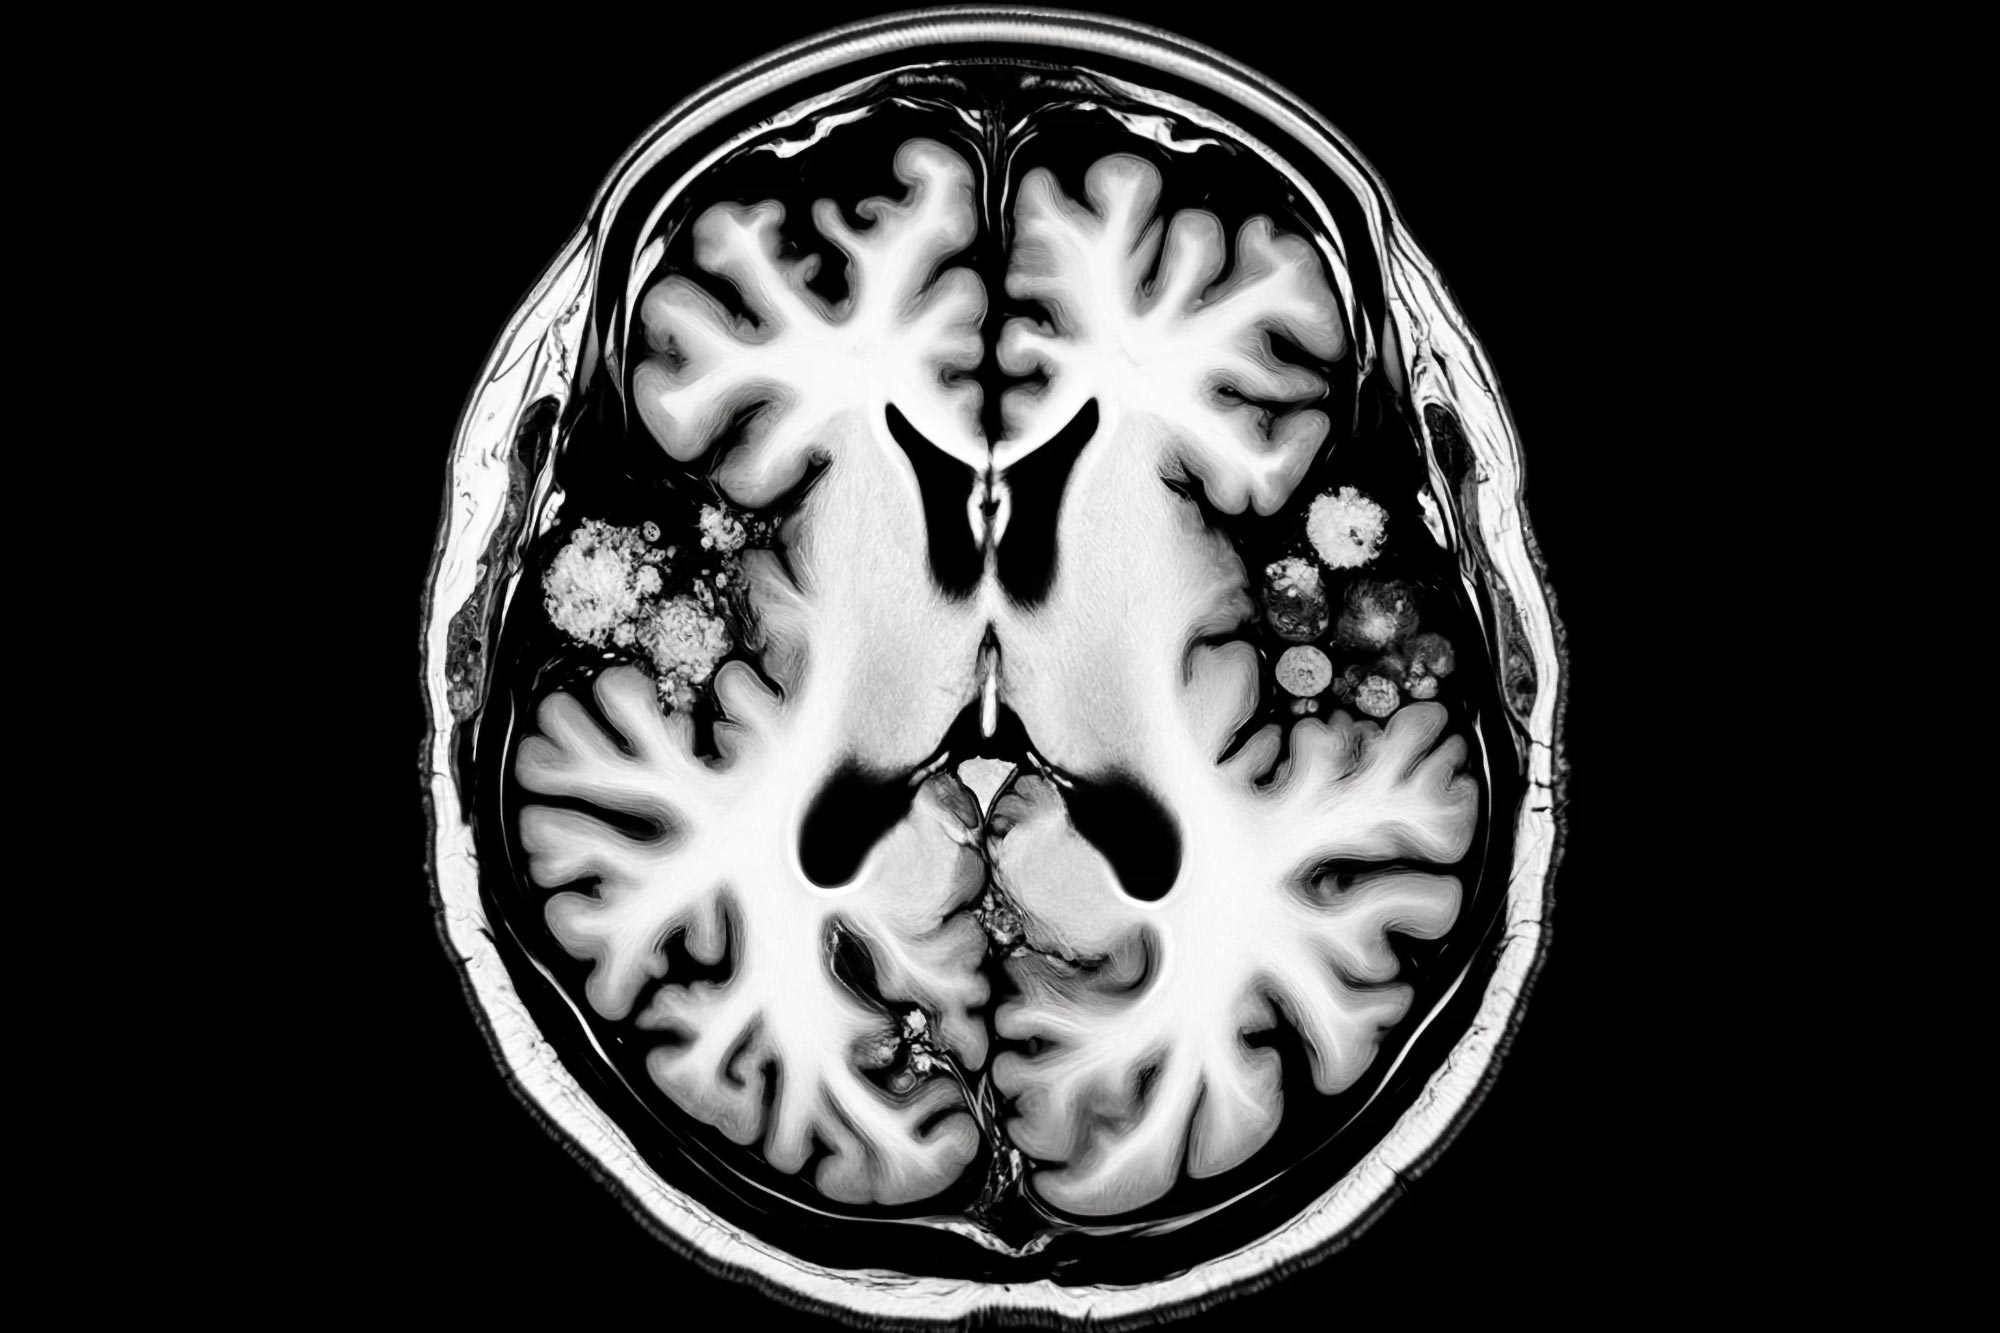

בעקבות אפיזודה של דלקת מוחית חמורה משאיפת פנטניל, אדם החלים בהצלחה בעזרת צוות רב-תחומי ב-OHSU, כמפורט ב- דיווחי מקרה של BMJ. מקרה זה משמש אזהרה לגבי השפעת האופיואידים על החברה. (קונספט האמן.) קרדיט: twoday.co.il.com

הדמיית תהודה מגנטית גילתה דלקת במוח. עם זאת, אובדן ההכרה, הזיכרון והתפקוד המתמשך של המטופל יכול היה לנבוע מכל מספר סיבות – שבץ מוחי, חשיפה לפחמן חד חמצני או מחלה מטבולית ביניהם. בסופו של דבר, בדיקת סמים לא סטנדרטית גילתה נוכחות של פנטניל במערכת שלו.